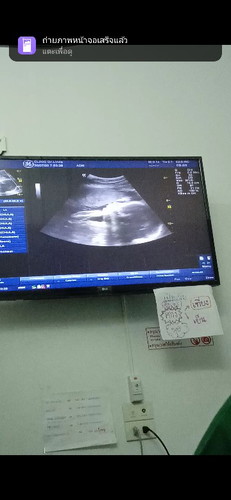

ลูกบ้านนี้ไม่ให้เห็นหน้าเลยคะเห็นแค่ด้านข้าง แม่ทีม พ.ย น้ำหนักลูกเท่าไรแล้วคะบ้านนี้ 26+3w 1032แล้ว จ้ำม้ำเกิน